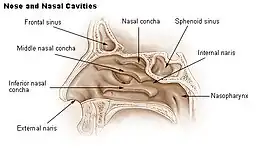

The cause of ENS is due to the body not accepting the new airflow in the nasal passages following surgical procedures. The nose is an incredibly complex area of the body and one that has been very poorly researched in terms of the effects on aerodynamics from surgical procedures. In many patients with ENS, the airflow is modeled as being more turbulent with less laminar flow across the mucosa. This change in airflow leads to an imbalance of CO2/O2 levels in the body, which will show hyperventilation-like symptoms in patients. This reduced amount of mucus in the nose can also be attributed to the change in airflow often resulting in dry cool air hitting the back of the patient's throat.

One possible cause may be changes to the nasal mucous membrane and to the nerve endings in the mucosa resulting from chronic changes to the temperature and humidity of the air flowing inside the nose, caused in turn by removal or reduction of the turbinates.[3][5] Direct damage to the nerves may be a result of surgical intervention; however, as of 2015, there is no technology that allows the mapping of the sensory nerves within the nose, so it is difficult to determine whether this is causative of ENS.[3] Investigators have been unable to identify consistent diagnostic or precipitating features, psychological causes leading to a psychosomatic condition have been proposed.[3][9][10][12]

It has been proposed, that the airflow in ENS patients is changed so that most of the air flows through the middle meatus, compared to most of the air flowing through the inferior meatus in healthy individuals. This can be corrected via inferior meatus augmentation (IMAP surgery).[19]

No consensus criteria exist for the diagnosis of ENS and many ENTs will wait a year before diagnosing in hopes the patient accepts the new airflow; it is typically diagnosed by ruling out other conditions, with ENS remaining the likely diagnosis if the signs and symptoms are present.[3][5][9] A "cotton test" has been proposed, in which moist cotton is held where a turbinate should be or in various locations in the nasal passages, to see if it provides relief and an airflow pattern that allows for natural breathing; while this has not been validated nor is it widely accepted, it may be useful to identify which people may benefit from surgery.[3][5][9]